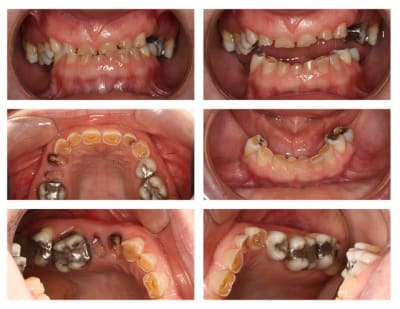

Femme de 39 ans

Histoire médicale RAS

Pas de douleur (ATM, muscles, dents RAS)

Demande solution globale/esthétique.

La 21 mesure 8,6 mm par 3,6 mm de haut...

hummm je crois qu'il y a usure...

18-28-24-25 sont à extraire.

Pas bcp d'os en bas...scan dans 1 semaines.

Si tu regardes les 13 et 23, l'architecture de osseuse/gencive est inversée pour 12-11-21-22. Allongement osseux d'au moins 2 mm, voir 3 mm. Perte de DV (profil écrasé en occlusion).

En postérieur, supra-éruption marquée de 16 et 26 (aussi 17 et 27), presque en occlusion avec la crête du bas (pire en secteur 2).

Implants 24 et 25 (exo 18-28-24-25).

Si on perd 16-26 et 17-27 (paro), on placera des implants.

Phase 1 en bas : 9 couronnes (endo, allongement) et prothèse (implants plus tard, si possible) ou bien on vire tout et transvissé sur 6 implants en bas...c'était l'idée de la patiente.